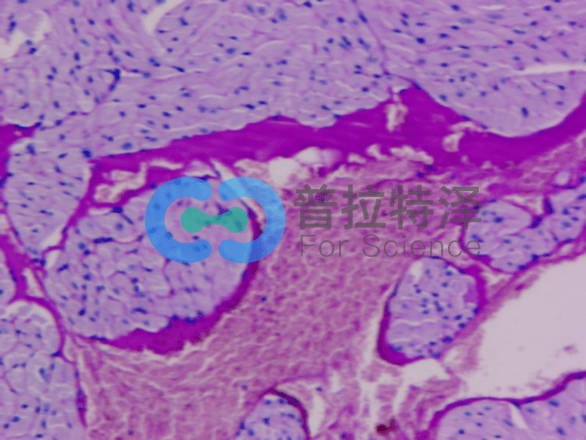

在生物學和醫(yī)學領域,PAS染色(Periodic Acid-Schiff Stain)是一種常用的組織染色技術,用于檢測組織中的多糖類物質,如糖原和粘多糖。掌握PAS染色的正確步驟,對于科研人員和醫(yī)學工作者來說至關重要。普拉特澤生物——組織染色實驗平臺操作各類組織的染色實驗上百例,專業(yè)代做PAS染色和各種染色實驗,本文將從入門到精通,全面介紹PAS染色的步驟和注意事項。

→Schiff試劑染色:將氧化后的切片放入Schiff試劑中,醛基與Schiff試劑中的亞甲基藍發(fā)生反應,形成紫紅色產(chǎn)物。

→蘇木精復染:用蘇木精對切片進行復染,使細胞核呈現(xiàn)藍色。